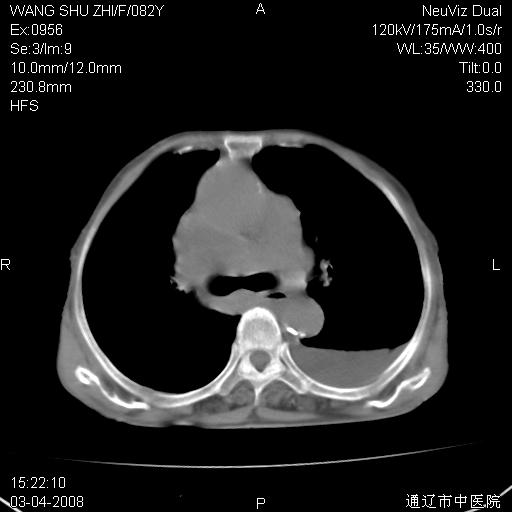

该患者为女性,82岁,既往肺心病、心衰病史。上纵隔影增宽,是否为畸形扩张的血管呢?因该患者年龄太大,又有较严重心脏病,故不适宜做增强检查。

中纵隔肿块最多见是淋巴瘤,而且以hd为多见,呈侵袭性生长,纵隔脂肪间隙消失,再加上心包和双侧胸腔积液,考虑为淋巴瘤(hd)应该说比较准确的。至于说是畸形的血管可能性小,因为畸形血管周围脂肪间隙应该存在。

纵隔淋巴结转移或淋巴瘤;双侧胸腔积液,心包积液。肺窗呢?

病史太简单,年龄太大,首先考虑转移!左侧腋窝亦见肿大淋巴结。

左侧腋窝及纵隔内见多个肿大淋巴结影,左侧少量胸腔积液,心包积液,支持淋巴瘤可能性大,不除外淋巴结转移。